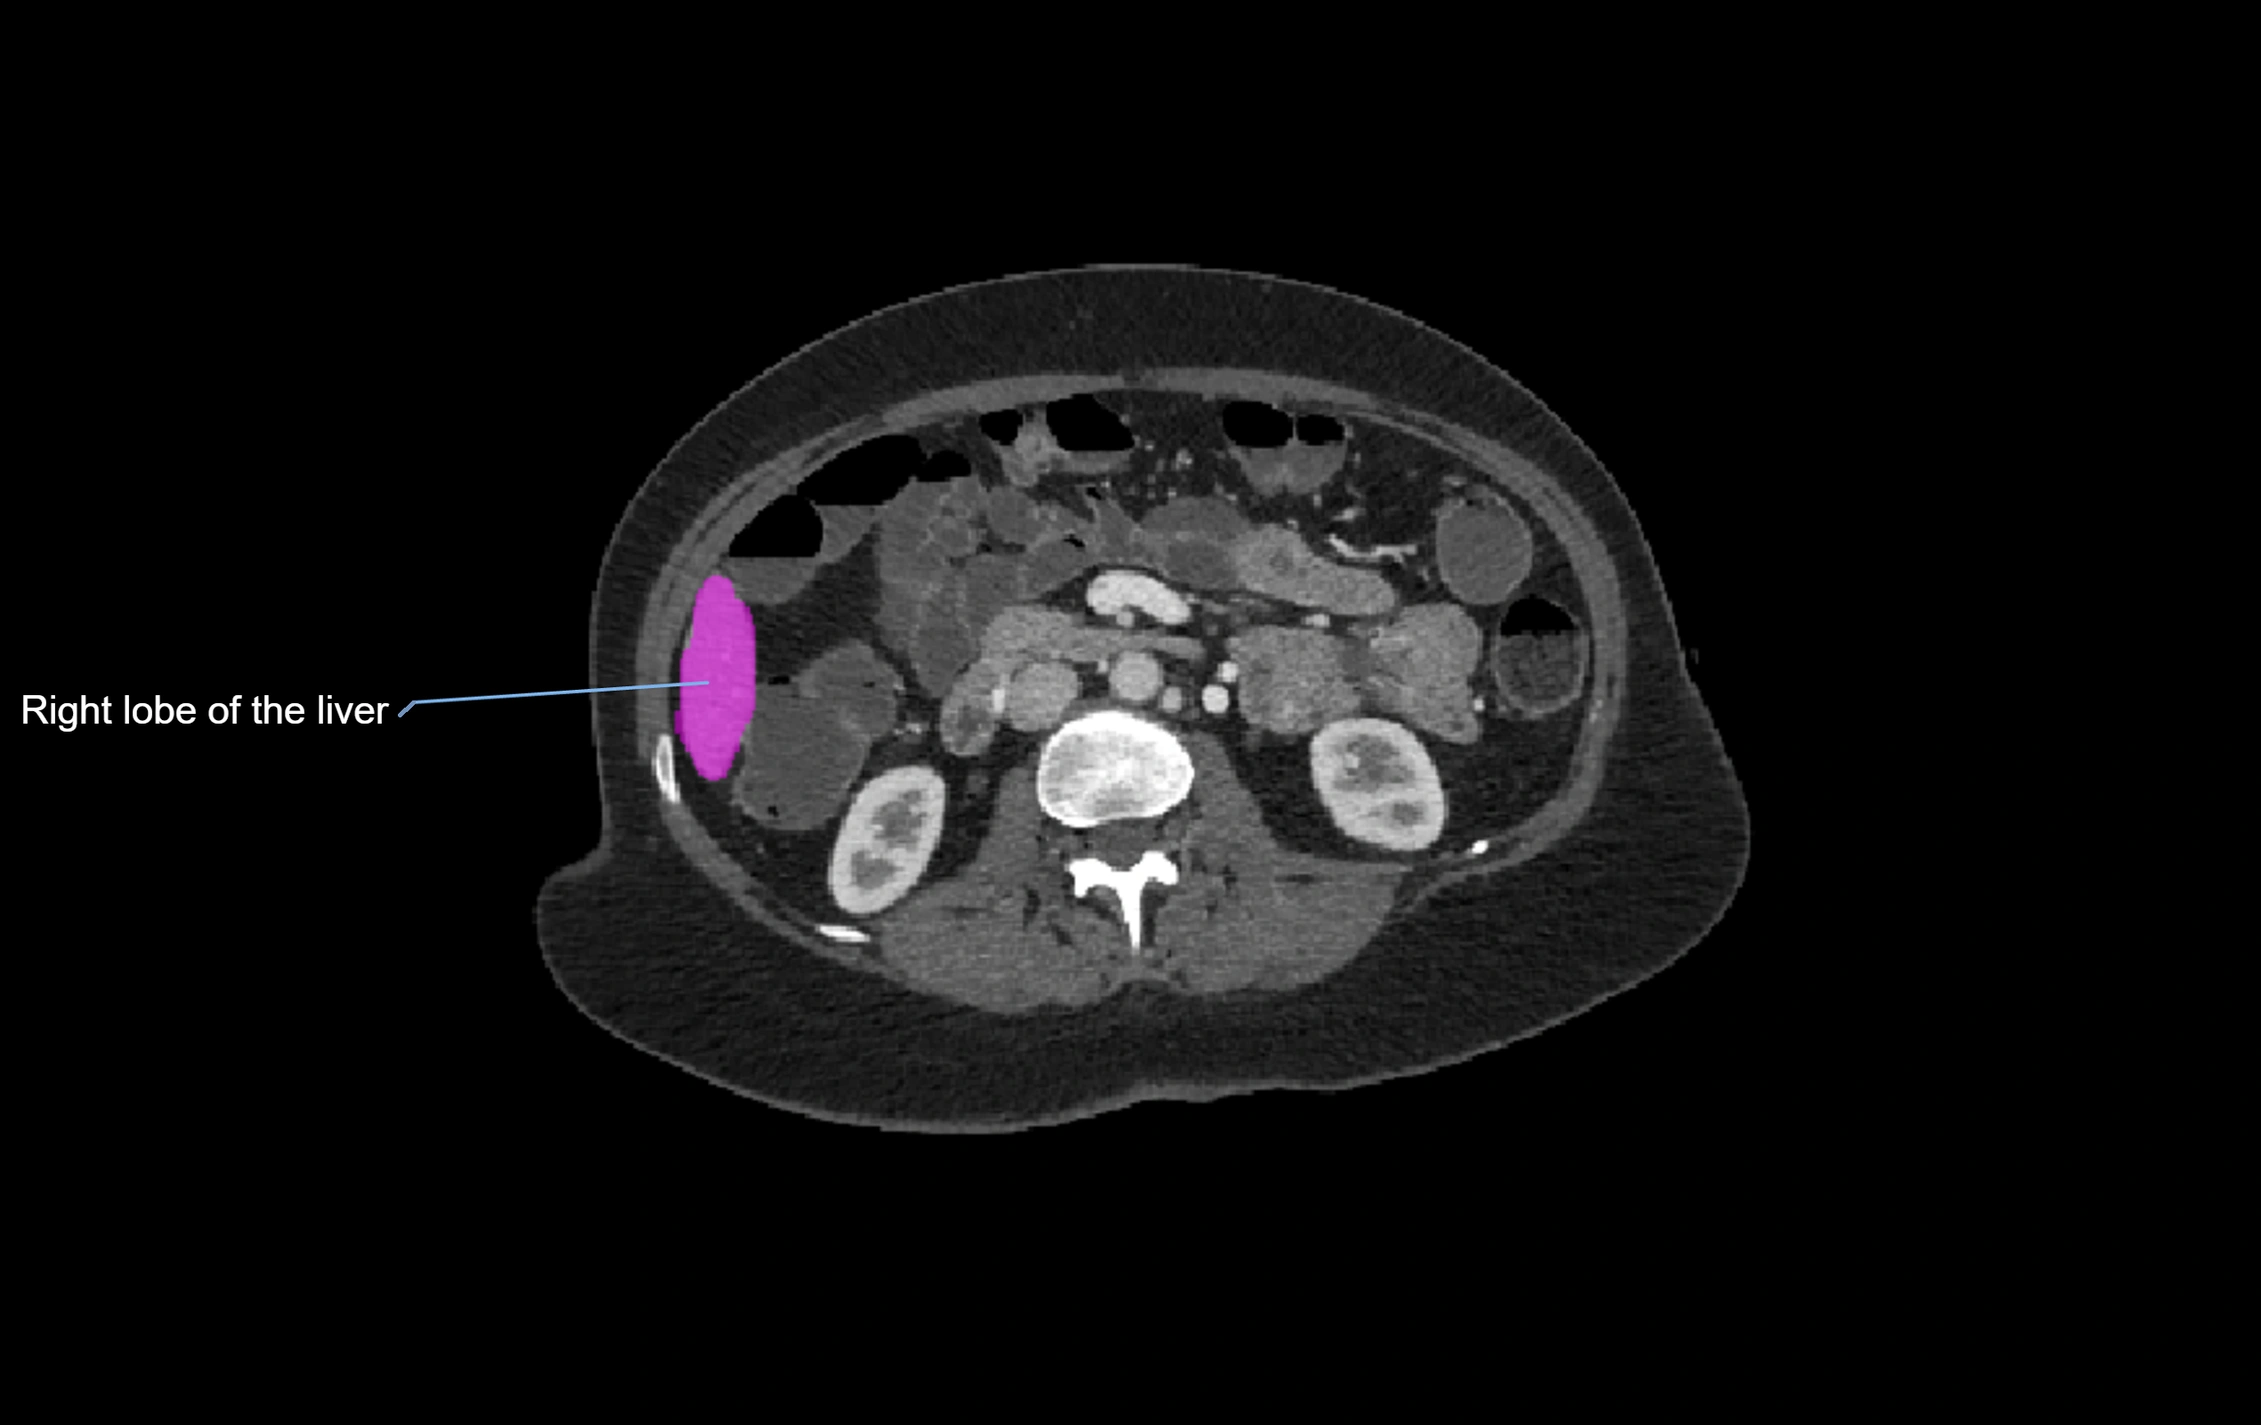

CT Image

image